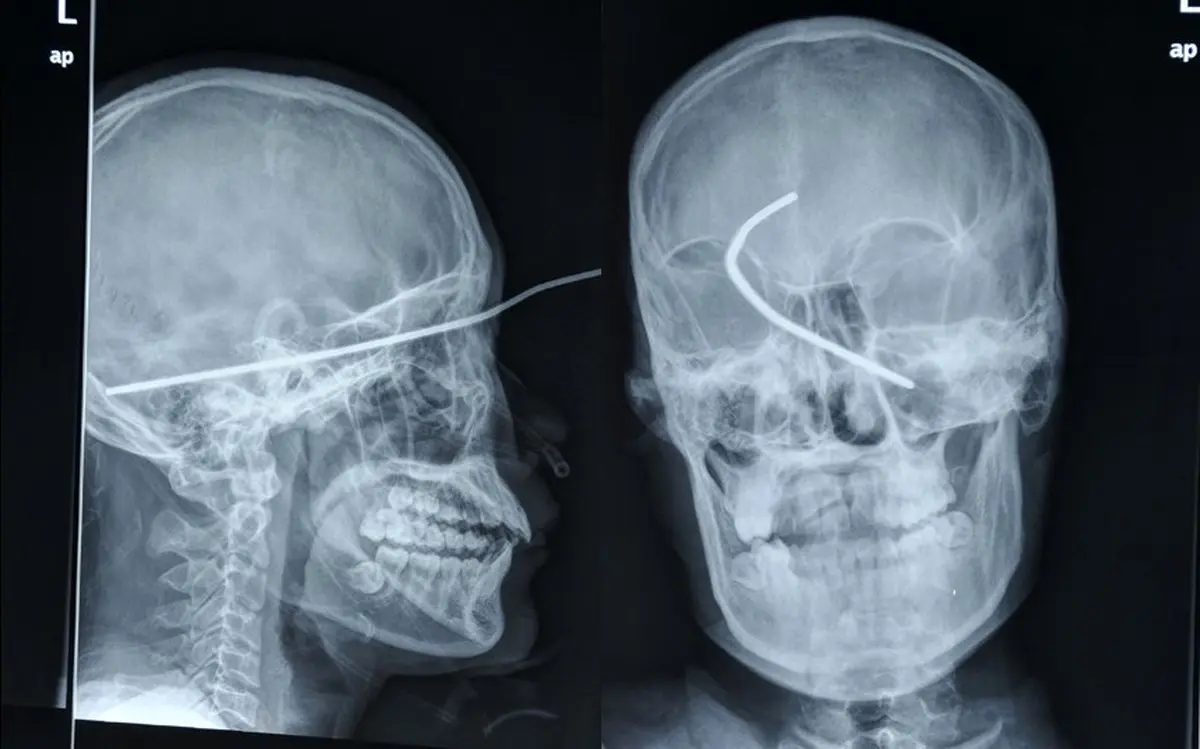

رکنا: عکس رادیولوژی اشعه ایکس که میلهای فرو رفته در سر آقای ها وی در گانگزهو چین را نشان میدهد.

این مرد چینی بعد از فرو رفتن یک میله جوشکاری در سرش زنده ماندهاست. در لحظه این اتفاق، ها وی روی نردبانی ایستاده بود و سایهبانی را جوشکاری میکرد. پسر عموی او میگوید: «او از بالای نردبان افتاد، اما زود بلند شد و حتی برای یک تا دو دقیقه ایستاد و گفت که حالش خوب است. اما وقتی که روی خود را برگرداند، یک میله جوشکاری بلند از سرش بیرون زده بود.

او خیلی سریع به بیمارستان منتقل شد و در آنجا پزشکان به مدت ۵ ساعت او را تحت عمل جراحی قرار دادند تا آن میله ۱۹ سانتیمتری را از سرش بیرون بکشند. از این ۱۹ سانتیمتر، ۱۴ سانتیمتر در داخل سرش فرو رفته بود. سرپرست بخش جراحی آقای وو تایهو میگوید: «این میله تنها در فاصله ۲ میلیمتری شریان اصلی و در فاصله ۵ میلیمتری رگ گردن قرار گرفته بود. و اگر هر کدام از این شریانها آسیب میدیدند، ممکن بود در همان لحظه بیمار بمیرد. میله در مغز بیمار رفته بود و تا وقتی که به استخوان جمجمه در آن سوی مغز برخورد نکرد از حرکت باز نایستاد. معمولاً در این مواقع شانس زنده ماندن بسیار کم است. اما او از آن نظر خیلی خوششانس بوده است».برای ورود به کانال تلگرام ما کلیک کنید.